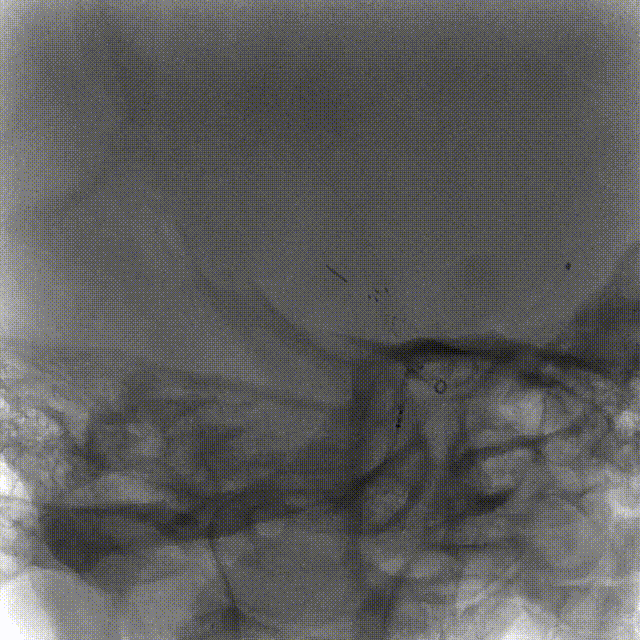

完全释放FRED 4017血流导向密网支架辅助弹簧圈栓塞后,正、侧位及3D造影观察,载瘤动脉通畅、支架贴壁良好、动脉瘤内造影剂滞留。

4个月后随访DSA,右侧颈内动脉正、侧位造影可见瘤颈缺损处内皮化修复,动脉瘤治愈。